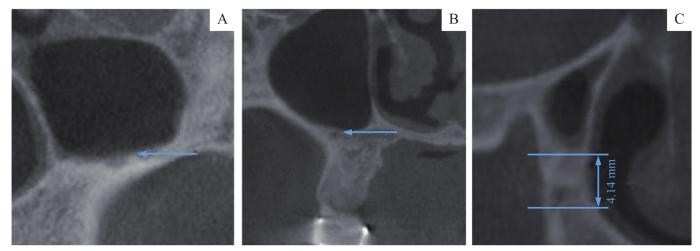

(2)MSA走形类型:按照走形位置与上颌窦侧壁的关系,对MSA走形(图1)分类为窦内型(位于上颌窦黏膜下方)、骨内型(完全位于上颌窦侧壁骨壁内)、表浅型(位于上颌窦侧壁骨膜下方)。

MSA走形类型

Note:A. Intrasinus type. B. Intraosseous type. C. Superficial type.

Fig 1

Shape type of MSA